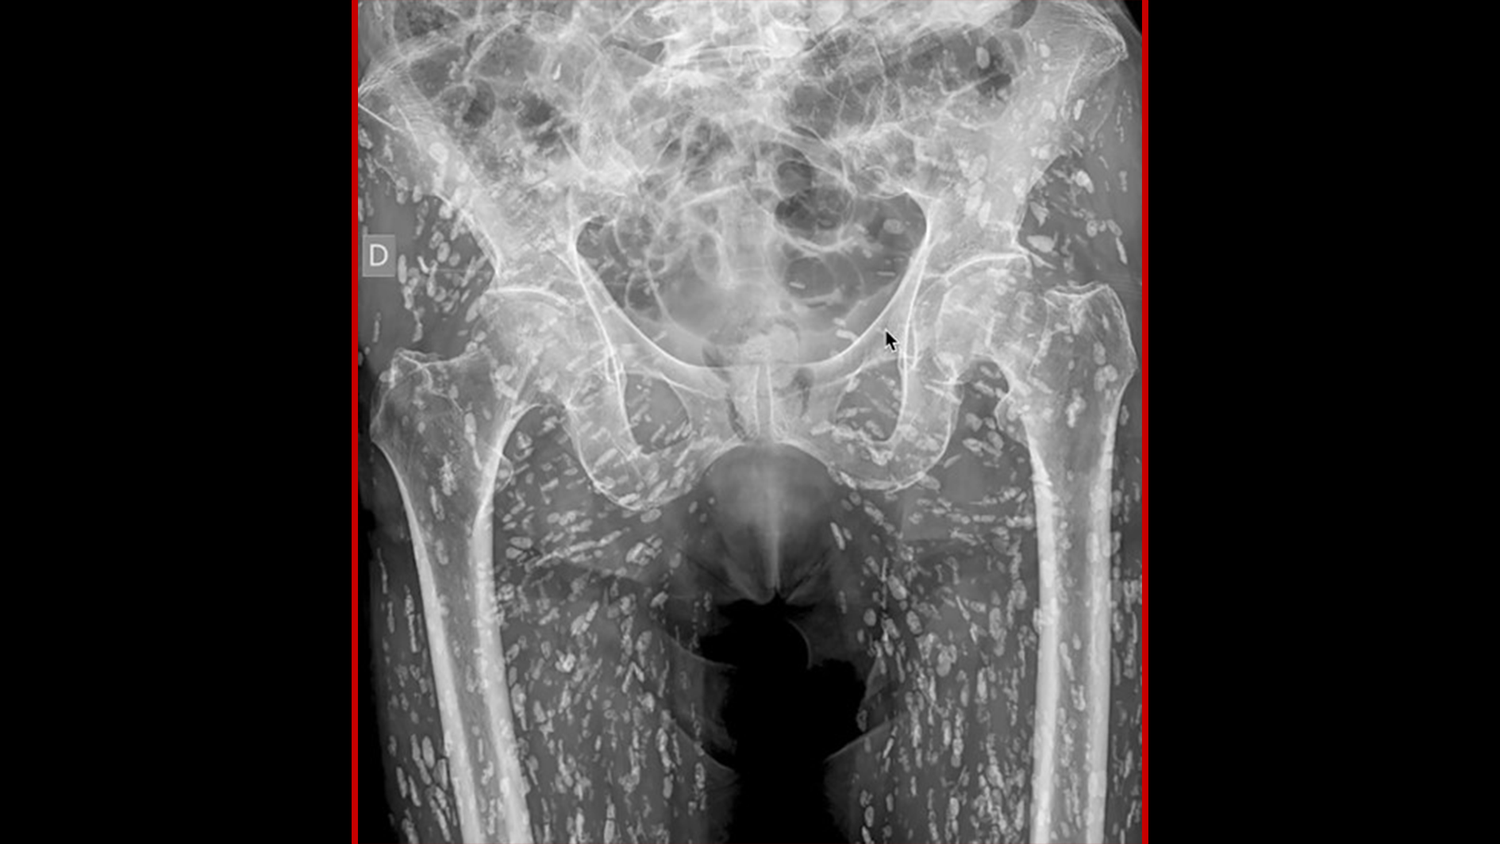

Das Röntgenbild des Patienten (oben).